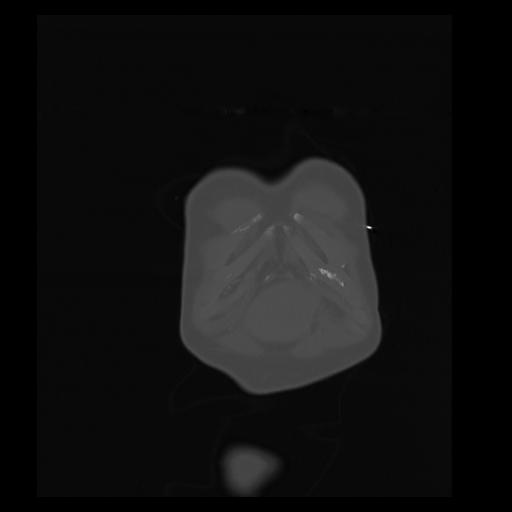

32 PULMON,CE,Coronal,3.000,PULMON,Coronal,